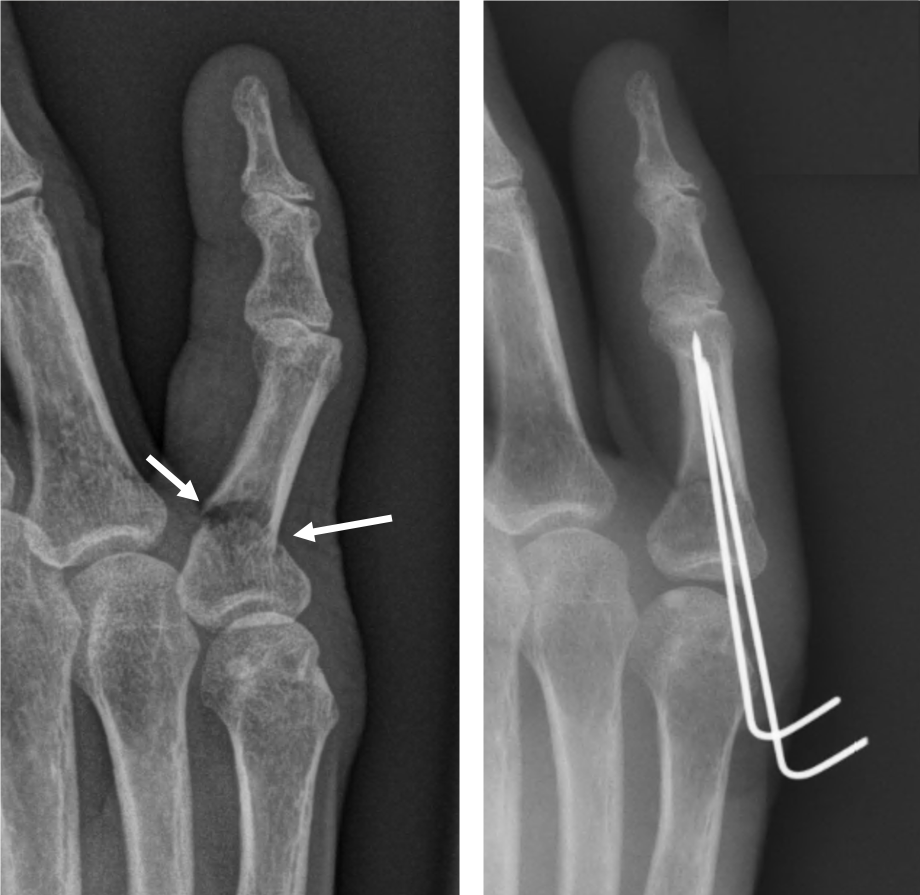

손가락 골절 스플린트 치료

손가락 골절에서 스플린트는 가장 기본적이면서도 중요한 치료 수단입니다. 손가락은 작은 뼈들이 관절과 밀접하게 연결되어 있어, 정확한 위치 고정이 이루어지지 않으면 기능 저하로 이어질 가능성이 높습니다.

손가락 스플린트는 골절 위치에 따라 착용 각도와 형태가 달라집니다. 예를 들어 말단지 골절의 경우 손끝만 고정하는 단순 스플린트가 사용되며, 중간 마디나 관절 침범 골절의 경우 손가락 전체를 포함하는 고정이 필요할 수 있습니다. 스플린트 착용 기간은 대개 3-6주이며, 이후에는 점진적인 관절 운동이 병행됩니다.